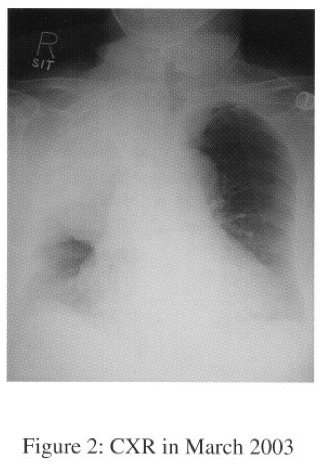

In Sept 2003, she was admitted to NDH for progressive dyspnoea and cough. CXR showed huge right lung opacity with right sided pleural effusion (Serial CXRs shown on figures 1-3).